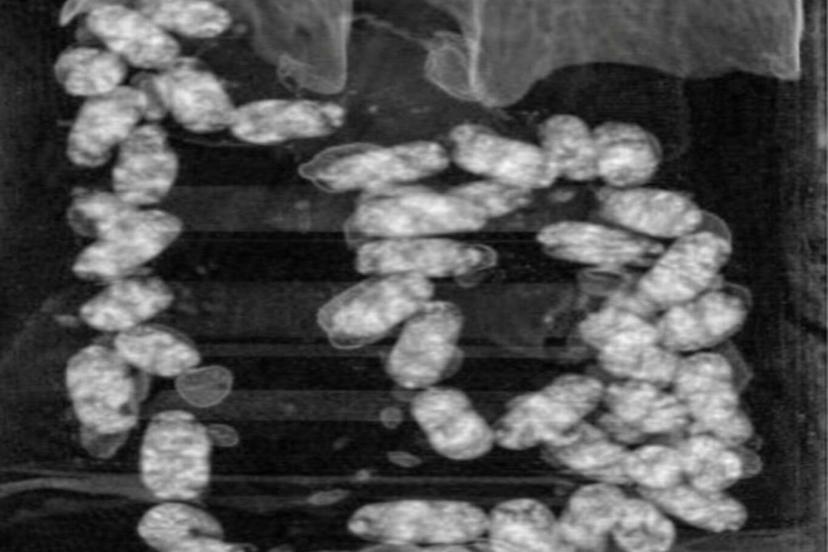

Narkotik Suçlarla Mücadele Şube Müdürlüğü ekiplerince yurt dışından İzmir’e "yutmak" suretiyle uyuşturucu madde getirilmesi üzerine operasyon başlatıldı.

Yapılan teknik ve fiziki takip sonucunda kimlikleri tespit edilen şahıslar, İzmir Adnan Menderes Havalimanı’nda yakalandı.

Şüpheliler üzerinde yapılan iç beden muayenesinde, 105 kapsül halinde yutulmuş vaziyette toplam 965 gram metamfetamin ele geçirildi.